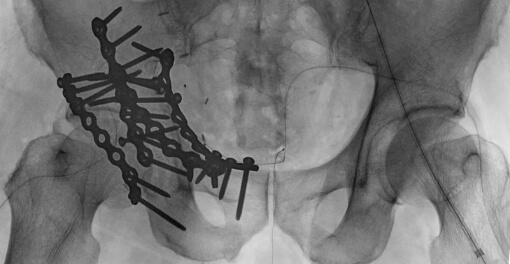

寛骨臼骨折症例

粉砕の強い右寛骨臼骨折の症例。前方・後方アプローチによる観血的整復固定術を行いました。